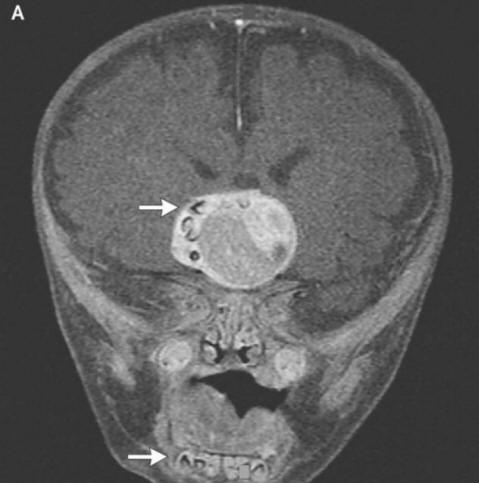

fénykép nyílt forrásból, ahogyan a sebészek elmondták a rémült szülőknek és onkológusok, ennek oka egy ritka veleszületett képződmény volt daganatok – craniopharyngiomas – írja a New England Journal of Medicine. Ez a daganat az esetek túlnyomó többségében jóindulatúak azonban egyre nagyobb lehet egy golyó – golf és okozza a szaglás, a hallás és látás romlását, és – szintén növeli az intrakraniális nyomást. A kutatók mindig gyanította, hogy ezek a daganatok már gyermekkorban megjelennek a fogakkal azonos sejtekből kialakult terhesség, mivel nagy kalciumfelhalmozódást észleltek, de egy valódi formájú fogat, amelyet ebben az esetben nem találnak elszámolni.

A sebészek sikeresen eltávolították a fényképet a nyílt forrásokból mondták, hogy a fiúnak jól van. Azonban egy fog, hogy nőtt fel az agyalapi mirigyében, de mégis megrontotta az agyat, megfelelő hormontermelés – a betegnek ezeket előbb be kell szednie az élet vége. Ez az eset jogosan büszke lehet a helyre az onkológusok legfurcsabb műveleteinek listája. Időközben iráni fiatalember, akinek kellett kezelje szőrös szemét. Szinte furcsa tumor jelent meg a szemében közvetlenül a születés után, de 19 éves korukra 2006 – ban jelentősen megnőtt méretét (legfeljebb 0,6 cm), és megakadályozta ezen felül a szemhéjak bezárását merev haj kezdett növekedni. Az orvosok eltávolították a tumort, és azt találták ez egy limbális dermoid – rendkívül ritka, általában jóindulatú oktatás. Az orvosok szerint ebben az esetben ha a fiatalember továbbra is gyógyszeresen húzza, akkor duzzanatot jelent nemcsak a hajat növeli, hanem izzadni is kezd: az idő múlásával daganatokban a megfelelő mirigyek gyakran megjelennek.